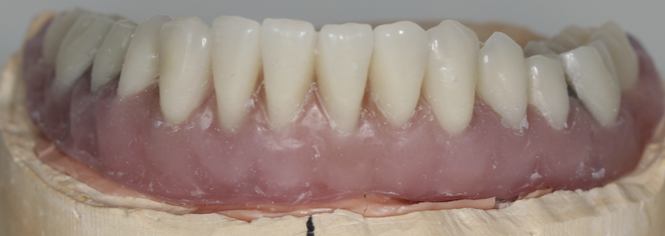

Mai întâi se realizează bara (Fig. 3.9.10) peste care se va aplica viitoarea lucrare. Apoi se realizează o machetă a lucrării pentru a analiza corectitudinea ocluziei (mușcăturii) (Fig. 3.9.11) precum și înălțimea dinților și aspectul facial al pacientului (Fig. 3.9.12, și Fig. 3.9.13).

Proteza stă pe bară fără să se miște deoarece în baza protezei există elemente de ancorare siliconate de culoare galbenă așezate aproape una de cealaltă pe toată suprafața bazei (Fig. 3.9.14). Acele elemente creează fricțiune între proteză și bară și nu permite desprinderea involuntară a acesteia, chiar dacă pacientul mestecă alimente lipicioase. Proteza poate fi îndepărtată cu mâna doar printr-o acțiune voluntară a pacientului. Acest tip de lucrare reface funcția masticatorie, pacienții bucurându-se de toate tipurile de alimente fără grija că proteza va cădea sau va sări.

Aspectul lucrării este unul natural, aceasta îmbunătățind estetica generală și fizionomia pacientului prin redarea conturului feței și plenitudinii obrajilor și a buzelor. Refacerea funcției masticatorii și redarea fizionomiei va aduce o îmbunătățire semnificativă a calității vieții pacienților care aleg acest tip de tratament (Fig. 3.9.15).